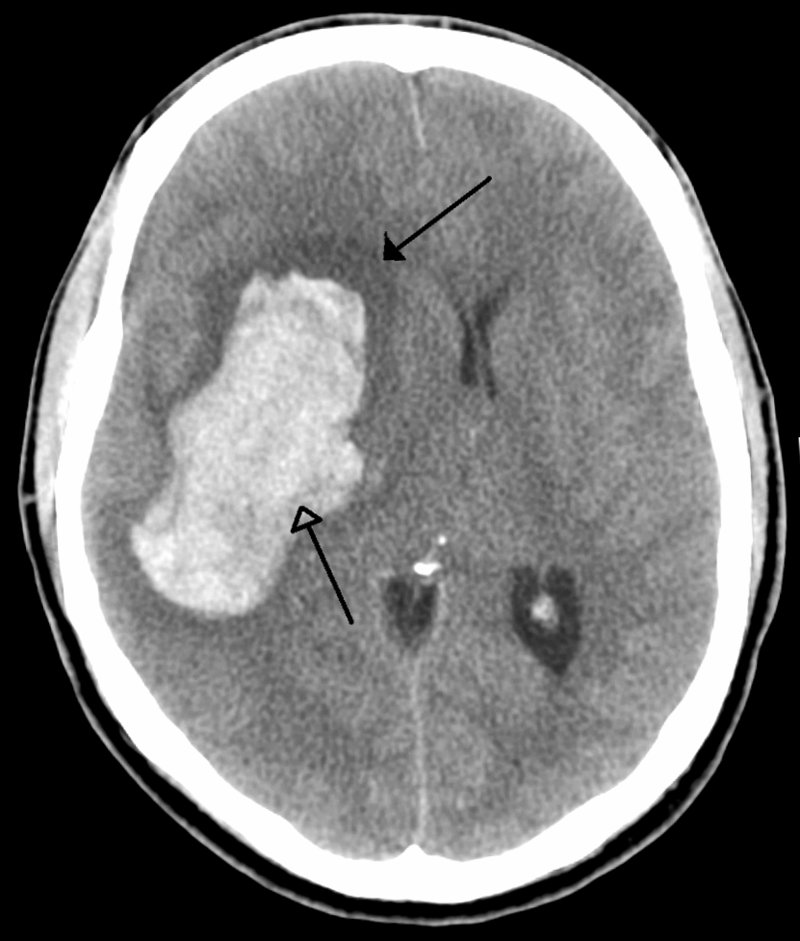

Intracerebral Hemorrhage

An intracerebral hemorrhage is due to brain parenchyma bleeding.

Intracerebral hemorrhage may result from:

- Lenticulostriate vessel rupture

- Aneurysm rupture

The most typical location of the brain involved by intracerebral hemorrhage is the basal ganglia.

Intracerebral hemorrhage hemorrhages may be caused by hypertension.

Hypertension treatment decreases the risk of intracerebral hemorrhage by half.